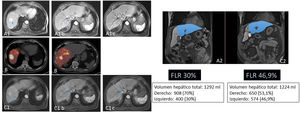

Paciente de 69 años con hepatocarcinoma binodular. No enfermedad a distancia. Función hepática conservada. Se aprecian dos lesiones en la resonancia magnética en segmentos VII y VIII (A). En imágenes A1b y A1c se aprecia que la lesión del segmento VIII está en contacto con la vena suprahepática derecha. Esto, unido al hecho de que el remanente hepático tras una hepatectomía derecha sería de 30% (A2), hicieron que se plantease la realización de una RE con la doble finalidad de downstaging e hipertrofia del remanente hepático. En el estudio PET-90Y (B) tras la administración por la arteria hepática derecha de 1,5 GBq de 90Y-microesferas de resina, se comprobó la adecuada llegada del tratamiento a las lesiones tumorales (dosis absorbida media de 185 Gy) y al tejido no tumoral hepático derecho (dosis absorbida media de 76 Gy; V30 56%). A los cinco meses de la radioembolización se comprobó (C1) la separación de la lesión del VIII de la vena adyacente (C1b y C1c), junto a una adecuada hipertrofia del remanente (C2). El paciente fue tratado mediante hepatectomía derecha laparoscópica (no requirió transfusión; tres días de ingreso). En la fecha de la última revisión (72 meses tras la cirugía), el paciente seguía vivo y libre de enfermedad.